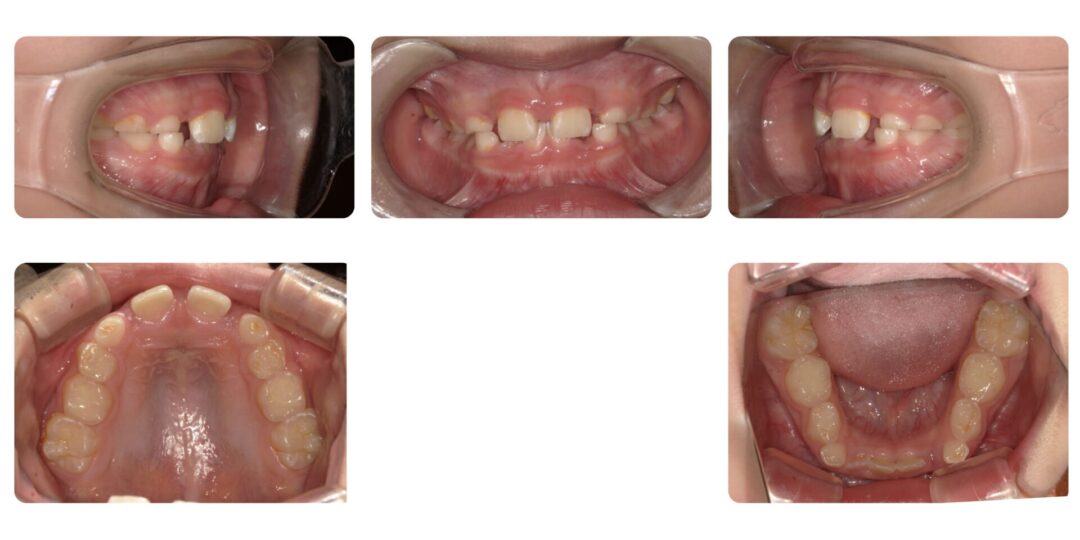

過蓋咬合を伴うアングル2級咬合|初診時7歳

矯正治療前